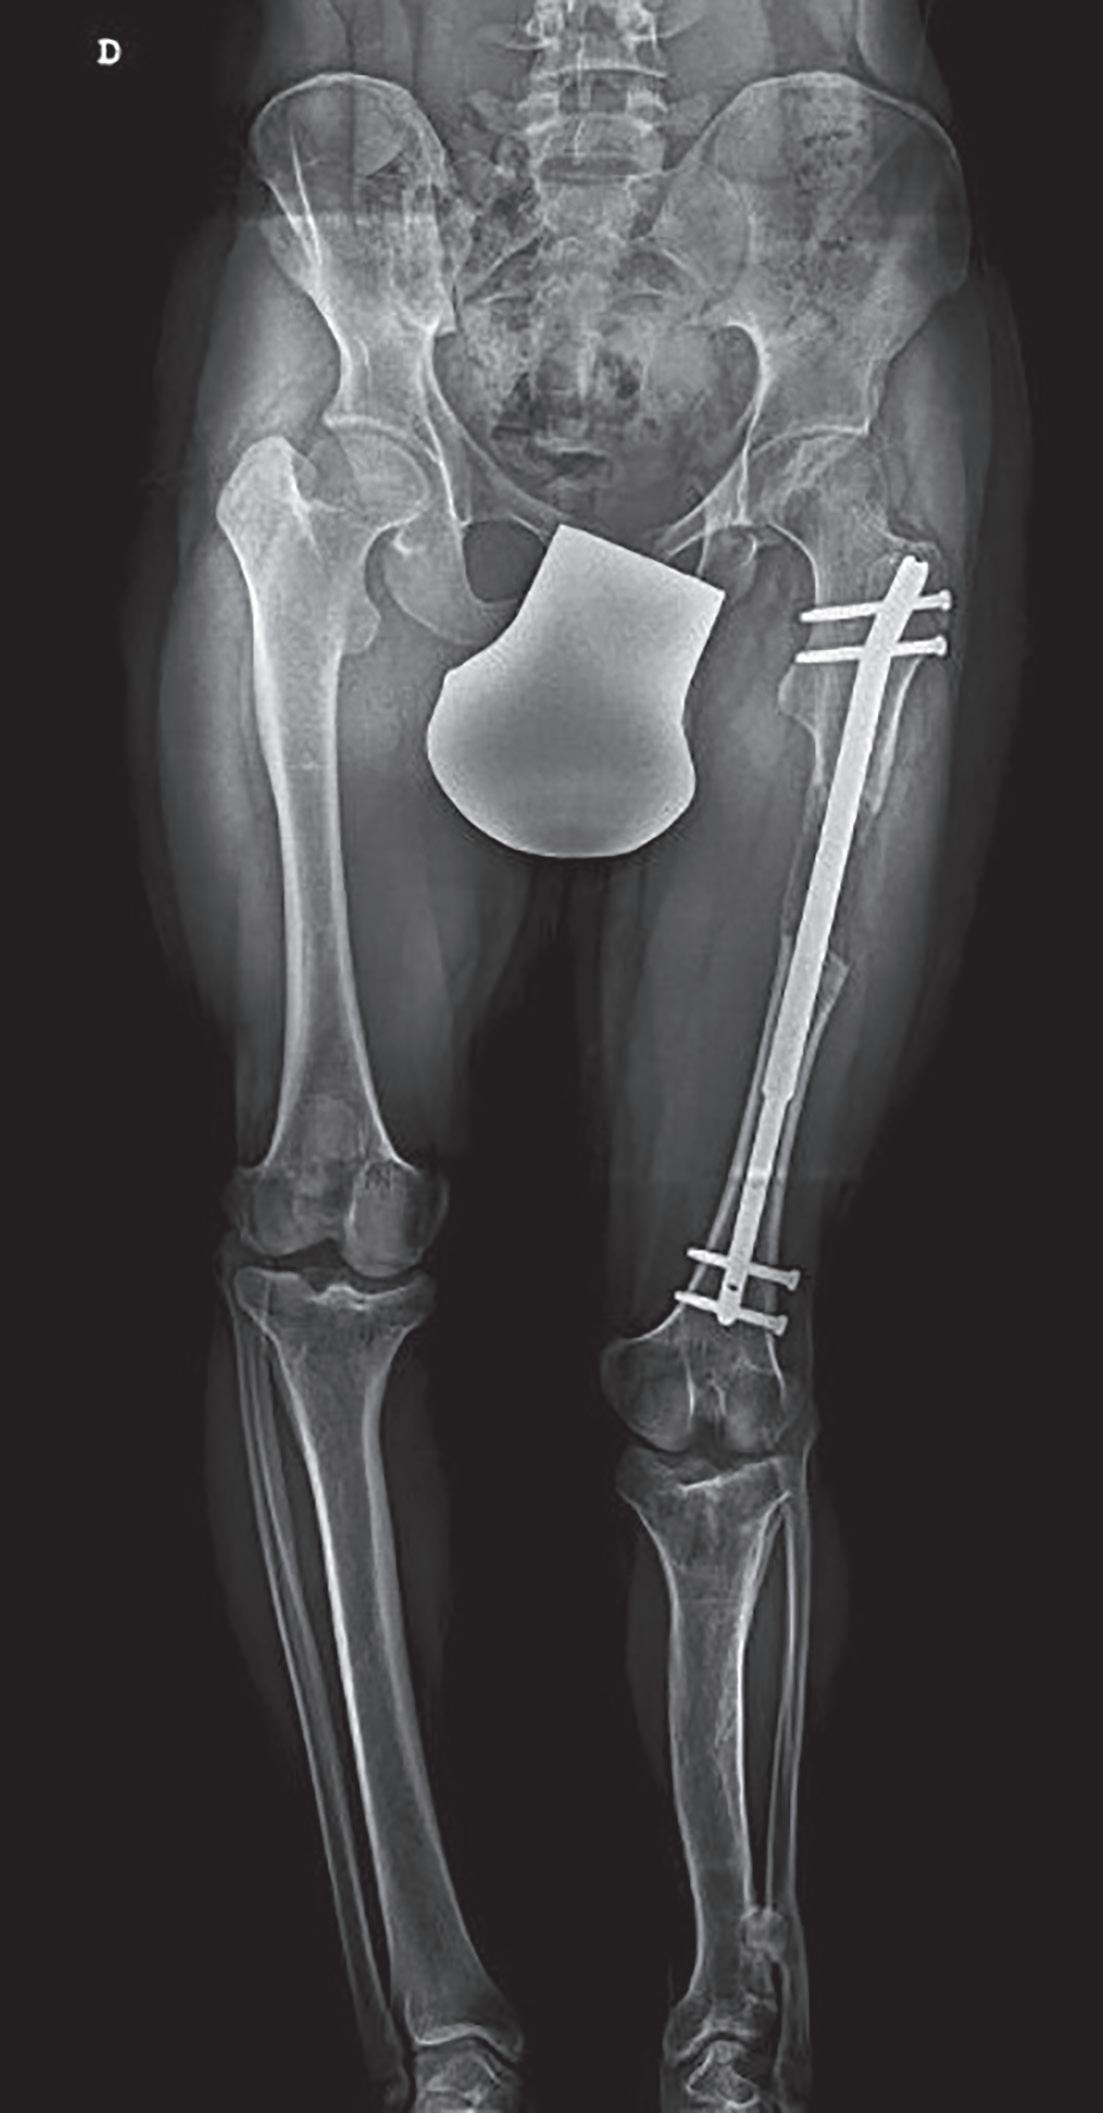

Figura 17.4 – Radiografia de paciente com escoliose neuromuscular. Destaque para curva com formato de um “C” longo, o desequilíbrio pélvico e as alterações ao nível das articulações coxofemorais.

Figura 42.2.3 – Imobilização gessada pelvipodálica, ou espica gessada. Em crianças acima dos 4 anos de idade, a preferência geralmente vai para varetas elás ticas intramedulares (figura 42.2.4), ou osteossíntese com placa. Em adolescentes próximos da maturidade esquelética, o encavilhamento endomedular com vareta aparafusada será, sempre que possível, a opção ideal. O fixador externo poderá ser uma opção no politrauma e em fraturas expostas.

Figura 42.2.4 – Encavilhamento endomedular retrógrado do fémur, com varetas elásticas flexíveis de titânio.